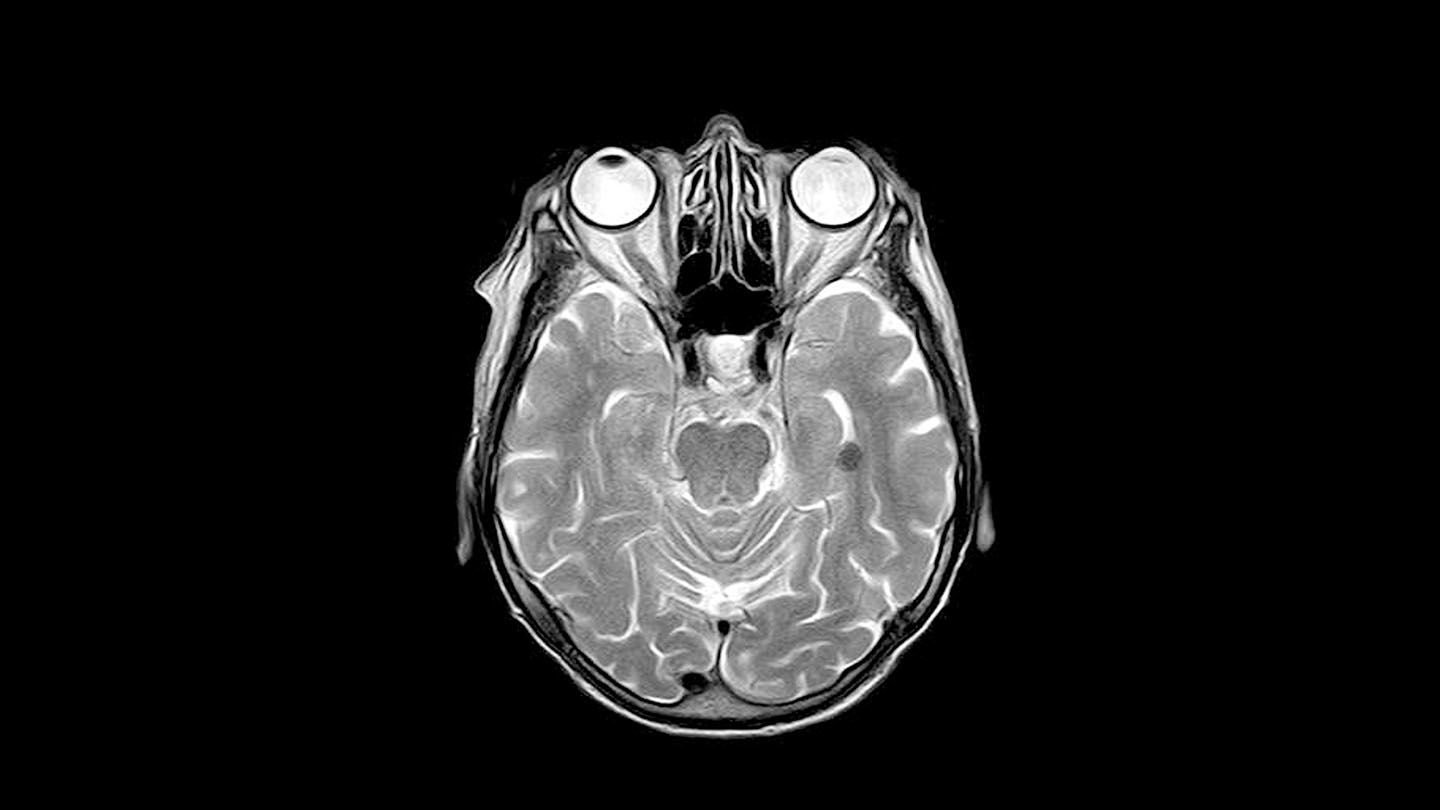

Ett viktigt verktyg för barncancervården är den så kallade MR-kameran, som bland annat används för att diagnosticera hjärntumörer. I dag behöver barn oftast...

Barncancerforskning: Forskare har fått ny kunskap om vad som händer med barns hjärnor när de strålas. Den kan leda fram till att man i framtiden bättre ska kunna skydda mot...

Forskningsreportage: Det är vanligt att barn som fått strålning mot tumörer i hjärnan får kognitiva problem senare i livet. Men nu har forskare med finansiering från Barncancerfonden...